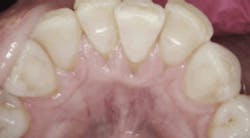

Periodontal charting on June 8, 2016.